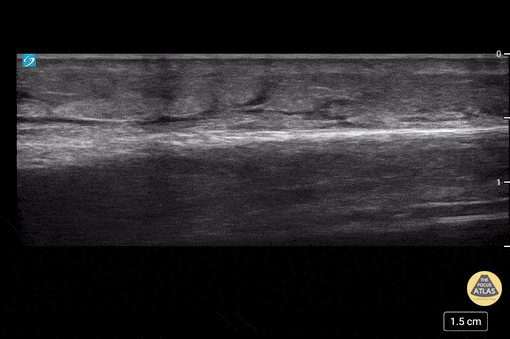

Soft Tissue - Cobblestoning in Cellulitis

This is an example of “cobblestoning”. This patient initially presented to the emergency department with lower anterior leg pain, especially with walking. Physical exam revealed minor erythema but also exquisite tenderness to palpation as well as with plantar flexion. Although cellulitis is clinically diagnosed, point of care ultrasound can be used to support it. The cobblestone presence is a result of edema between subcutaneous fat. Dr. Carlo Zamora, DO, PGY-1 Riverside Regional Medical Center Emergency Medicine Residency (Newport News, VA)